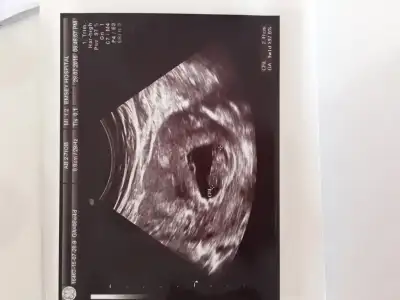

Son fotoğrafımız :)

masalahhhhh canm buyumus bebısınnnSon fotoğrafımız :)